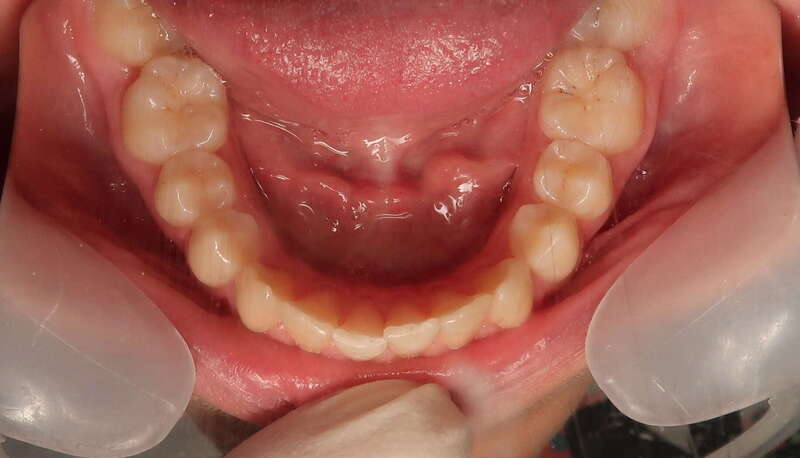

Cas n°12 traité par multi-attaches - adolescent

L'examen initial révélait une situation complexe nécessitant une action sur l'alignement et sur l'emboîtement des mâchoires :

• Encombrement bimaxillaire : Un manque de place important aux deux arcades (supérieure et inférieure), entraînant des chevauchements dentaires et des rotations gênant à la fois l'esthétique et l'hygiène.

• Prognathie dentaire inférieure : Les dents du bas se situent trop en avant par rapport aux dents du haut. Sans correction, ce décalage empêche un engrènement stable et peut fragiliser le parodonte des incisives.

• Sourire irrégulier : L'alignement défaillant brisait l'harmonie du sourire, avec des dents situées hors de la courbe idéale.

Éléments clés du résultat (Photos "Après")

La réussite de ce traitement a reposé sur une mécanique de précision et, surtout, sur une coopération sans faille de la patiente :

1. Alignement et Nivellement : L'utilisation de bagues a permis de redresser chaque dent et de créer des arcades aux courbes fluides et régulières.

2. Gestion de l'Ancrage par Élastiques : Le port rigoureux d'élastiques intermaxillaires (entre le haut et le bas) a été l'élément moteur pour reculer le bloc inférieur et avancer légèrement le bloc supérieur.

3. Obtention d'une Classe I Canine et Molaire : Le résultat final montre un engrènement "en clé", où les dents s'emboîtent parfaitement, assurant la stabilité du traitement.

4. Harmonisation faciale : Le profil et le sourire sont désormais équilibrés, avec un soutien labial optimal.

Effets positifs du traitement pour la santé de la patiente

• Pérennité du Parodonte : En replaçant les dents du bas correctement par rapport au haut, on supprime les traumatismes occlusaux qui peuvent causer des déchaussements prématurés.

• Facilité d'Entretien : Des dents parfaitement alignées permettent un brossage efficace, réduisant drastiquement les risques de caries et de gingivites.

• Protection Articulaire : Un bon emboîtement garantit un fonctionnement sain des articulations temporo-mandibulaires (ATM), évitant les douleurs et les craquements à long terme.

• Confiance en Soi : La transformation d'un sourire encombré en un sourire aligné et harmonieux est un atout social et psychologique majeur pour une adolescente.

Légendes des photos avant/ après

• Photos "Avant" : « Encombrement sévère aux deux mâchoires avec un décalage marqué : les dents inférieures sont trop avancées, ce qui perturbe la fonction masticatoire et l'esthétique globale. »

• Photos "Après" : « Résultat final montrant un alignement parfait et un engrènement de Classe I. Ce succès est le fruit d'une excellente coopération de l'adolescente dans le port de ses élastiques de coordination. »